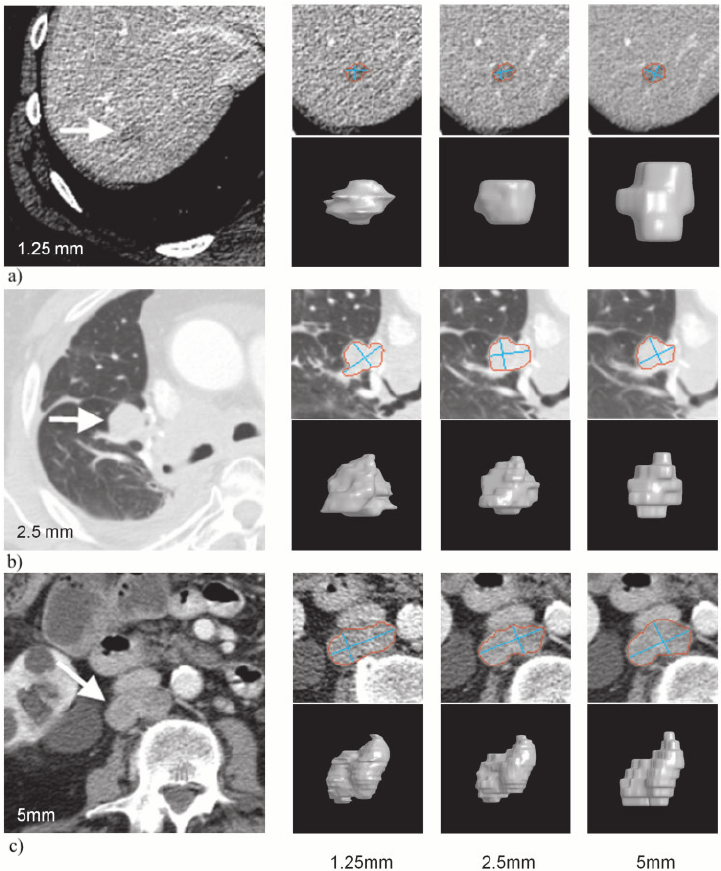

The results from all conducted experiments, represented as mean ±plus-or-minus\pm standard deviation, are tabulated in this section. We assessed the performance of our proposed simulation method against Simple Averaging, Gaussian Averaging, and Direct Downsampling. This was accomplished by simulating images with a thickness of 3mm from those with a thickness of 1mm, utilizing the 2016 Low Dose CT Grand Challenge dataset. The results outlined in Table III provide a comparative analysis of different thick-slice simulation methods used in two datasets from the 2016 Low Dose CT Grand Challenge. Both the PSNR and the RMSE were used as key performance indicators for these methods. The data clearly demonstrate that the proposed method significantly outperformed Simple Averaging, Gaussian Averaging, and Direct Downsampling in both datasets (D45 and B30). The highest PSNR values were obtained with the proposed method, yielding 49.7369 ±plus-or-minus\pm 2.5223 and 48.5801 ±plus-or-minus\pm 7.3271 for D45 and B30 datasets, respectively. The proposed method also registered the lowest RMSE with values of 0.0068 ±plus-or-minus\pm 0.0020 and 0.0108 ±plus-or-minus\pm 0.0099 for D45 and B30, respectively. These results indicate a superior level of accuracy and reliability in the proposed method. The statistically significant differences were confirmed by a Wilcoxon signed-rank test with p-value ¡ 0.05, implying that the improvements from the proposed method were not due to random chance. These findings support our first hypothesis that the proposed simulation method provides a more efficient and precise approach to thick-slice simulations compared to traditional methods. To provide a more comprehensive evaluation, visual comparisons from axial, coronal and sagittal plane were also undertaken, as depicted in Figures 2 to 4. In summary, Our proposed method demonstrated substantial enhancements in terms of both PSNR and RMSE, indicating a distribution more closely aligned with the authentic thick-slice image.

Refer to caption

(a) True Thick-slice image

(b) Simple Averaging

RMSE: 0.0329, PSNR: 35.6776

(c) Gaussian Averaging

RMSE: 0.0955, PSNR: 26.4221

(d) Direct Downsampling

RMSE: 0.0454, PSNR: 32.8776

(e) Proposed Simulation

RMSE: 0.0010, PSNR: 46.4076

Figure 2: Axial-plane thick-slice image quality comparison across four simulation methods.